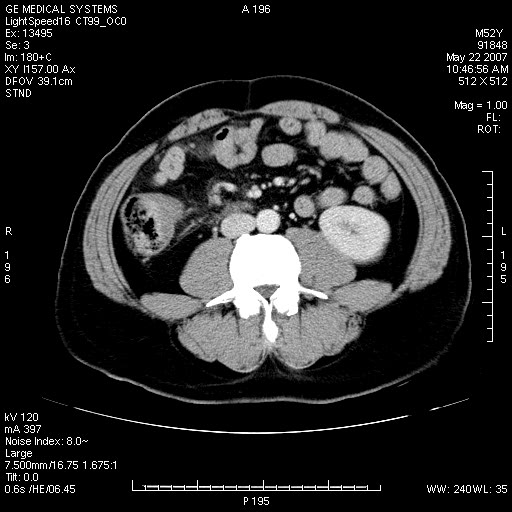

以下是引用余辉在2007-5-22 20:12:00的发言:[br]升结肠管壁明显增厚,增强有静脉期持续增强,结合患者病史,考虑结肠癌可能性大,临近脂肪影密度增高,混浊,恐有肠系膜浸润转移,建议镜检

以下是引用dyqct在2007-5-22 20:43:00的发言:[br]支持结肠肝曲占位性病变(浸润型结肠癌可能性大)。胆总管下端扩张,原因待查。

以下是引用gaoxiao在2007-5-22 20:49:00的发言:[br]考虑升结肠癌向周围侵犯,胰头钩突受侵。